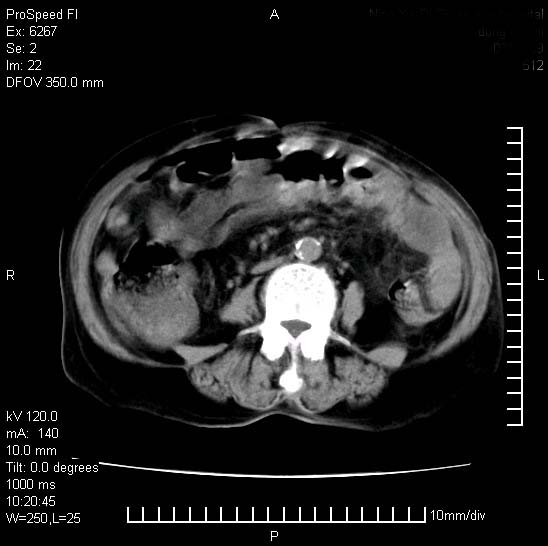

患者糖尿病,腹痛,恶心,呕吐。黄疸,意识较差,血糖很低(数值不详),临床以胆囊,胆管炎,低血糖反应收治。看的腹片少,各位帮忙看看,胰腺有问题吗??

1.胰腺体积增大,胰周脂肪间隙消失,胰腺炎可以确定。必要时实验室进一步检查。

胰腺体积增大,胰周脂肪间隙消失,考虑胰腺炎。胆囊炎,胆石症。

脾大,原因?胆结石;胰腺肿大,边缘模糊,建议查定性指标血尿淀粉酶,除外胰腺炎

1)考虑胰腺炎;建议查血尿淀粉酶。2)胆囊炎,胆囊结石。3)脾大。